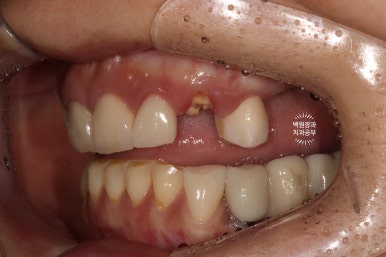

신경치료 후 크라운으로 씌웠던 치아셨는데, 이차충치로 인해 치아가 부러진 그 자리엔 짧은 뿌리 뿐이었습니다..

어금니가 없이 앞니로만 너무 오래 식사를 하시면, 이렇게 앞니가 부러짐을 경험하게 되시죠..

보시면 부러진 치아의 일부는 잇몸 속까지 포함해서 부러진 것을 볼 수 있었습니다.

그리고 치과용 CBCT 소견 상 송곳니 부위 잇몸뼈가 너~~무 적어 이 부위는 임플란트가 불가하고.. 양 옆의 치아를 이용한 지르코니아 브릿지 치료를 권해드렸습니다.